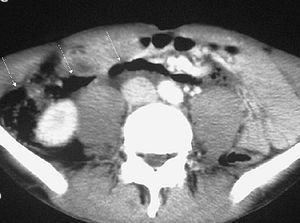

La causa más frecuente es la pancreatitis. Las enzimas pancreáticas pueden provocar una inflamación parietal del duodeno y estenosis de su luz. En procesos severos el componente inflamatorio llega a erosionar los vasos sanguíneos produciendo hemorragia duodenal e incluso puede provocar necrosis y perforación duodenal17 (fig. 10).

Fig. 10--Hematoma duodenal secundario a pancreatitis. (A) Colección líquida (flechas) en la pared del duodeno con aspecto quístico en la ecografía. AO: Aorta; VCI: vena cava inferior. (B) En la tomografía computarizada sin contraste intravenoso el hematoma (*) se observa como una colección hiperdensa en la pared duodenal.